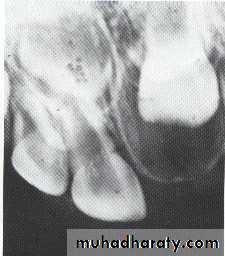

This cyst causes the roots of the central incisors to

diverge, and occasionally root resorption occur.

*Treatment by excision.